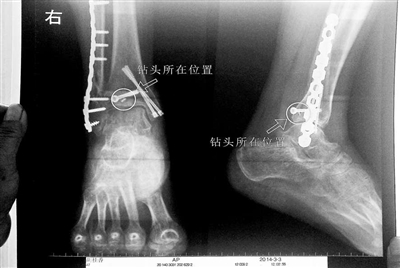

胡女士的腿部X光图

近日,在丰台区右安门医院,北京青年报记者见到了胡女士,她走起路来显得一瘸一拐,腿脚并不利索。在她带来的X光片上,可以清晰地看到,有一个异物存在于腿内部。

“我当时就吓蒙了,怎么会有一个钻头在骨头里?”胡女士余悸未消地说,第二天拍摄的X光片显示,2厘米左右的钻头遗留在她右脚脚踝上部的骨头内。

胡女士说,当时旁边的医生劝慰自己,称钻头留在腿里并不会有什么问题。出院后,胡女士每个月都会来医院做复查,拍X光片。她说,每次都能够清晰地看见自己骨头里的那个明晃晃的“小东西”。